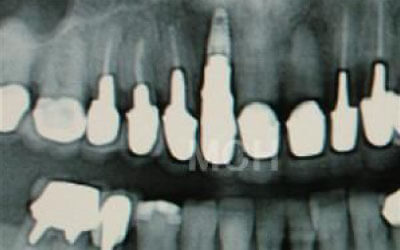

歯が抜けた後の治療について、多くの方が悩まれています。

特に、抜けたのが前歯ですとなおさら気になりますよね。 今回のご質問ですが、抜けた部分の骨が薄いなどの理由で「インプラントはできない」と言われた可能性があります。

前歯はもともと骨が薄く、歯が抜けると時間の経過とともにさらに骨が痩せてきてしまうので、インプラント治療の難易度が高い場所です。 ただ結論からお話すると、インプラント治療は可能です。

なぜなら、もし仮に骨が薄くても、骨の治療によって厚みが増せば、安全にインプラント治療が行えるからです。

なお、前歯のインプラント治療をご希望の方には、注意していただきたい点が4つほどあります。 1)インプラント治療を行う前に、骨の治療が必要かもしれません。

2)骨の治療から始めると、その分、治療期間が長くなります。

3)骨の治療は、通常のインプラント治療よりも難易度が高いため、経験の豊富な先生やインプラント認定医のいる歯科医院で治療を受けることをお勧めします。

4)骨の状況をしっかり把握するためにも、CT撮影が必須となります。 また、インプラント治療においては、周囲の歯の状況や咬み合わせの問題などもしっかりと考えて治療するのがとても大切です。

そのため、残っている歯についてもきちんと診査してくれるクリニックが良いでしょう。 インプラント治療には、「インプラントを入れたら終了」というイメージがありますが、治療後、どれだけ長くインプラントがもつのかが最も大切なことなので、しっかりとメンテナンスしてもらえる歯科医院を選んでください。 まずは、いくつかの歯科医院でインプラントの相談をして比較検討し、ご自身が良いと感じた先生のところで治療を受けることをお勧めいたします。